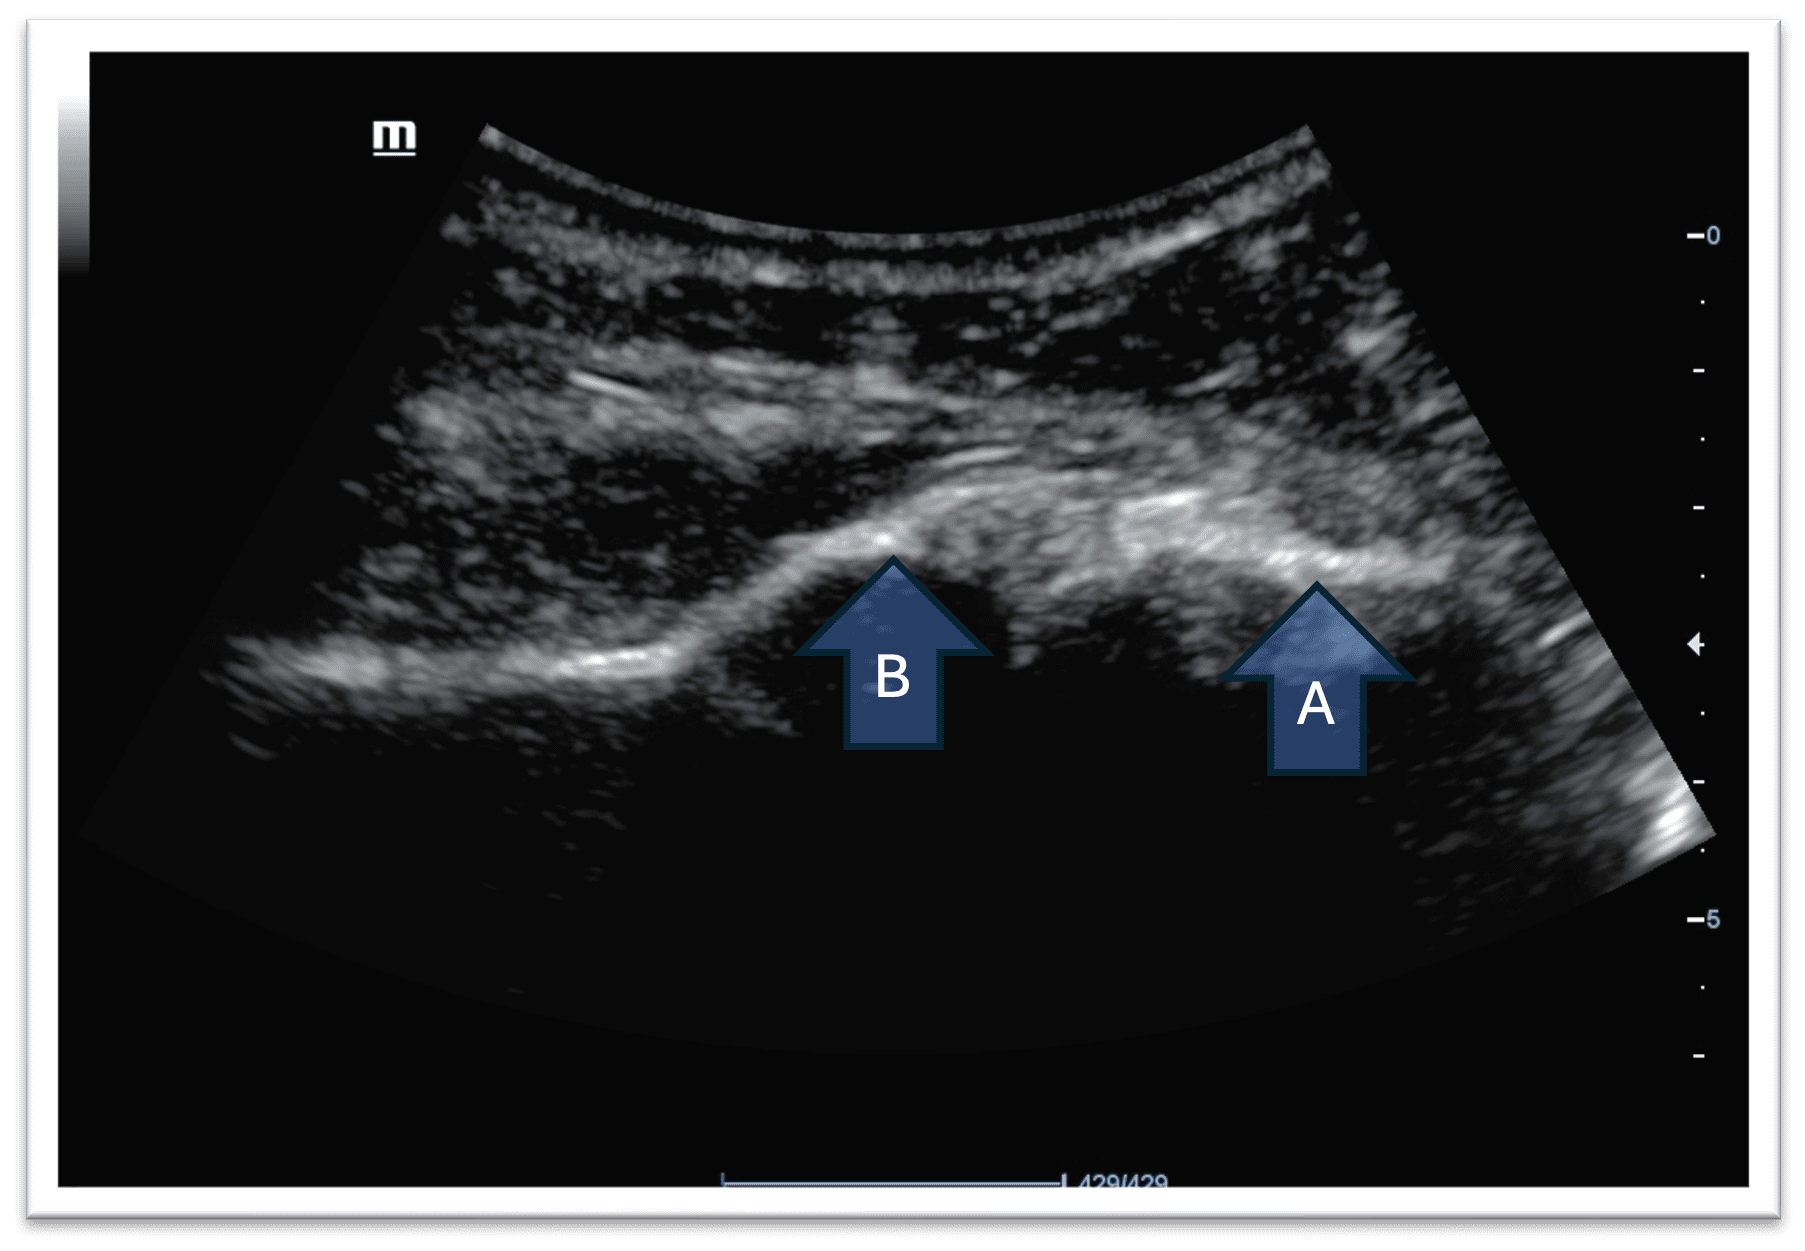

Figure 3. Ultrasound scan image of the right shoulder joint (posteriorly) The image left to right corresponds to the patient’s medial to lateral

Anterior

In a normal shoulder joint the head of the humerus will be located within the glenoid cavity. On ultrasound the glenoid rim and the head of the humerus will appear to lie in the same horizontal plane.

Figure 4. Normal Shoulder joint A – Head of humerus B – Glenoid

In this patient, the glenoid rim and the head of the humerus are not lying in the same horizontal plane. This indicates a dislocation.

Figure 5. Anterior dislocation of the shoulder

Note how the head of the humerus is located deeper in the image. This means that the head of the humerus is located further away from the probe. This is an anterior dislocation of the shoulder joint.

In the event of a posterior shoulder dislocation, the head of the humerus will appear closer to the probe.

Figure 6. Posterior dislocation of the shoulder A- Head of humerus B- Glenoid